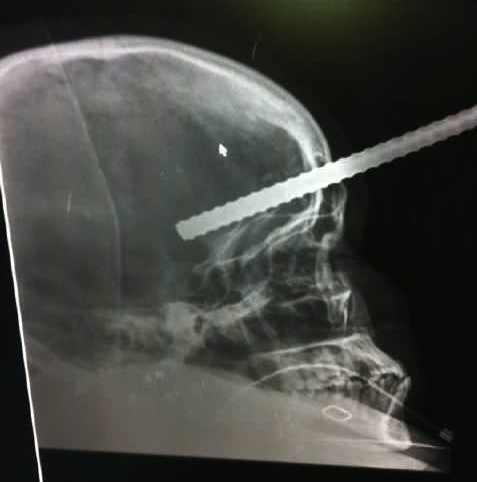

صورة من أشعة منسوبة للشهيدة صالح

مرآة البحرين: عبرت جمعية العمل الإسلامي (أمل) عن استنكارها لحفل أقامه المجلس الأعلى للمرأة الذي تترأسه حرم ملك البلاد سبيكة بنت إبراهيم آل خليفة اليوم بمناسبة يوم المرأة البحرينية. وقالت في بيان اليوم إن ذلك يأتي "في يوم سقطت فيه شهيدة منطقة الديه زهراء صالح (28 عاماً)" التي أصيبت بطعنة في الرأس بواسطة سيخ حديدي الشهر الماضي على يد قوات الأمن، وفيما ما تزال "ترزح فيه الكثير من المعتقلات في سجون السلطة".